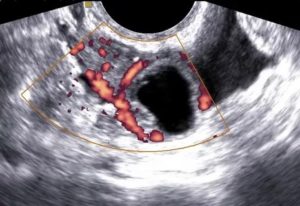

УЗИ снимок кисты желтого тела.

- УЗИ. В полости кисты отсутствуют кровеносные сосуды. Это является отличительной характеристикой лютеинового новообразования.

Уточнить диагноз позволяет УЗИ.